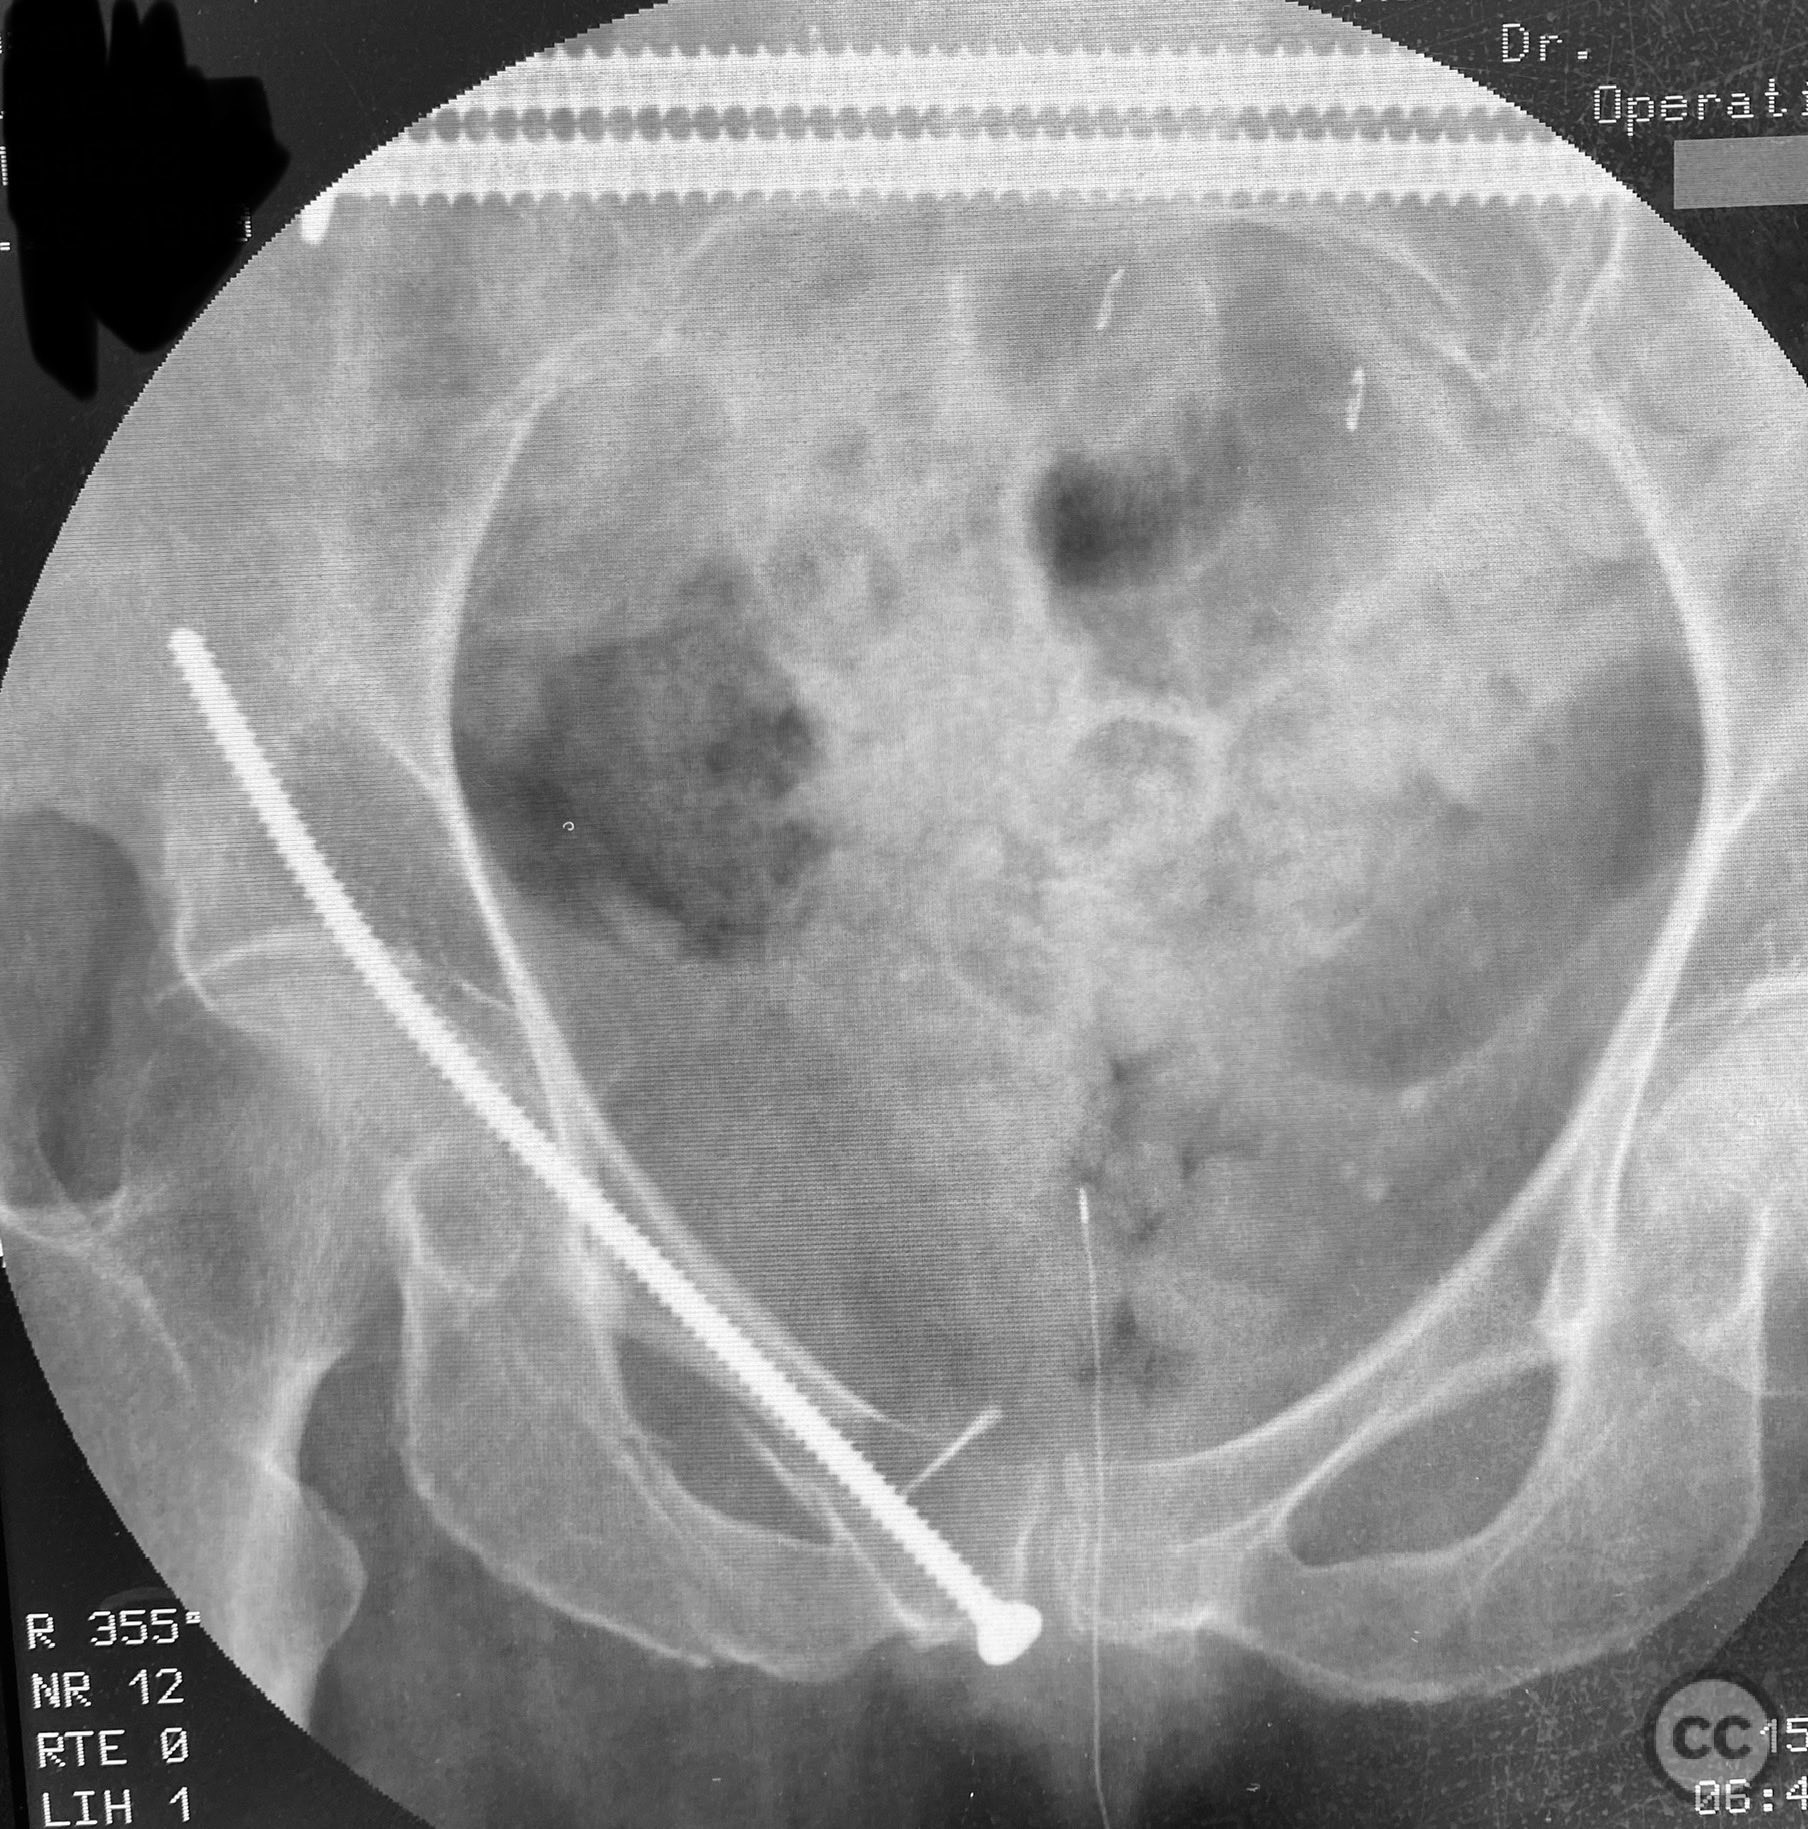

Anatomical surgical approach:  For the posterior fixation, a percutaneous approach was utilized targeting the upper sacral ala, with stab incisions made over the posterior superior iliac spine and blunt dissection to bone. Under fluoroscopic guidance, guidewires were advanced across the sacroiliac joint into the S1 body, followed by cannulated IS screw insertion. For anterior fixation, a small incision was made over the pubic tubercle, and a 4.5mm blunt tip cortical screw was introduced retrograde along the superior pubic ramus isthmus under fluoroscopic control, advanced by screwdriver along the dense lateral iliac bone.

Intraoperatively, EUAF confirmed instability sites and allowed dynamic assessment of reduction. IS screws were placed in the upper sacral path for posterior stabilization. The anterior ring was stabilized with a retrograde 4.5mm blunt tip cortical screw, advanced by turning with a screwdriver, utilizing the variable width of the ramus isthmus for optimal implant fit and stability. The technique permitted percutaneous fixation with minimal soft tissue disruption.